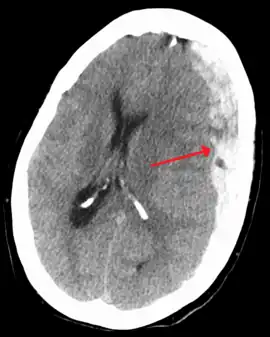

On a CT scan, subdural hematomas are classically crescent-shaped, with a concave surface away from the skull. However, they can have a convex appearance, especially in the early stages of bleeding. This may cause difficulty in distinguishing between subdural and epidural hemorrhages. A more reliable indicator of subdural hemorrhage is its involvement of a larger portion of the cerebral hemisphere. Subdural blood can also be seen as a layering density along the tentorium cerebelli. This can be a chronic, stable process, since the feeding system is low-pressure. In such cases, subtle signs of bleeding—such as effacement of sulci or medial displacement of the junction between gray matter and white matter—may be apparent.

Fresh subdural bleeding is hyperdense, but becomes more hypodense over time due to dissolution of cellular elements. After 3–14 days, the bleeding becomes isodense with brain tissue and may therefore be missed.[20] Subsequently, it will become more hypodense than brain tissue.[21]